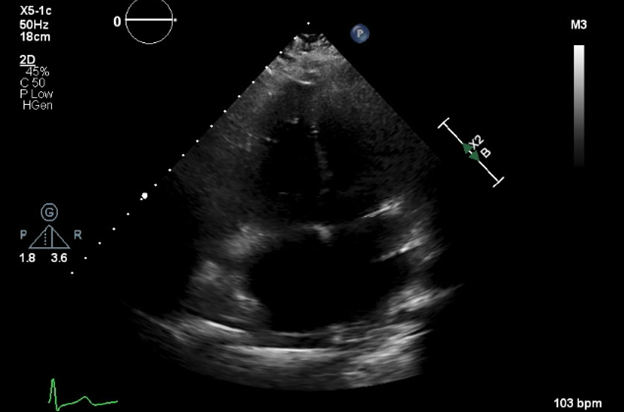

Case description: A 28-year-old female, on her 27th week of gestation (G4P3) was admitted to the hospital with preterm premature rupture of membranes. She also endorsed intermittent chest pressure, palpitations and shortness of breath. Her vital signs were stable, and electrocardiogram (ECG) revealed normal sinus rhythm with frequent premature ventricular contractions (PVCs) and T wave inversions in leads V1- V3. Laboratory studies showed normal troponin and D-dimer levels, and slightly elevated brain natriuretic peptide 240 pg/mL. Patient notably had frequent runs of monomorphic non-sustained ventricular tachycardia (NSVT) arising from RV apical territory, with left bundle branch morphology on telemetry. An echocardiogram revealed a dilated right atrium and RV with hypokinesis of RV; LV size and function were normal. Overall, patient met the revised task force diagnostic criteria for ARVD based on PVC morphology, abnormal ECG and dilated and hypokinetic RV. She had no sustained or hemodynamically unstable VT, no history of syncope or family history of sudden cardiac death and did not meet class I indication for implantable cardioverter defibrillator. She was started on oral metoprolol succinate 25 mg daily with which her arrhythmias significantly improved. She was recommended a cardiac magnetic resonance imaging and genetic testing for confirmation and to assess familial implications.